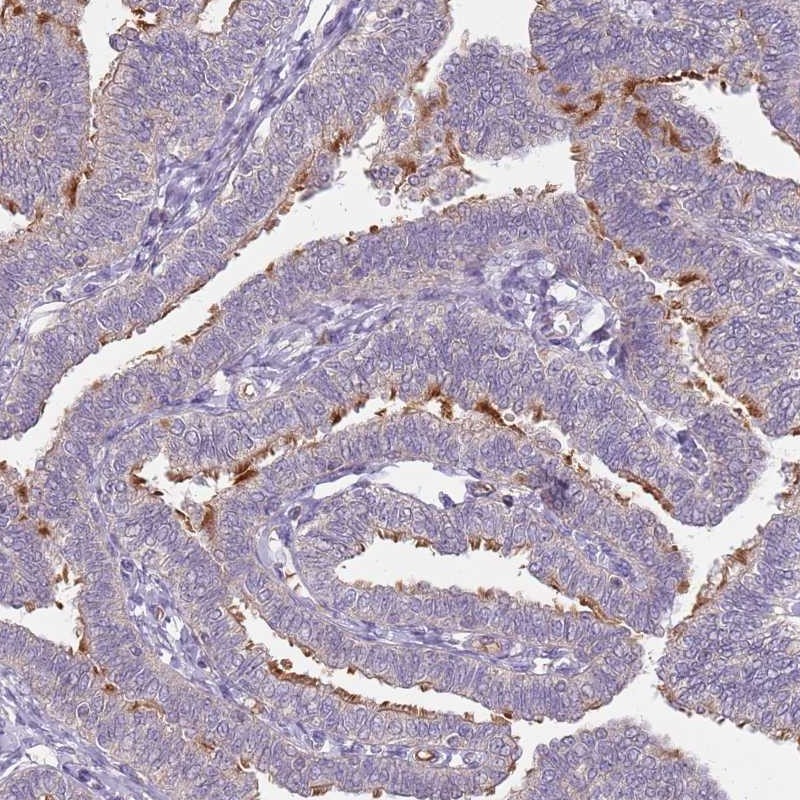

Immunohistochemical staining of human fallopian tube shows distinct positivity in cilia of glandular cells.